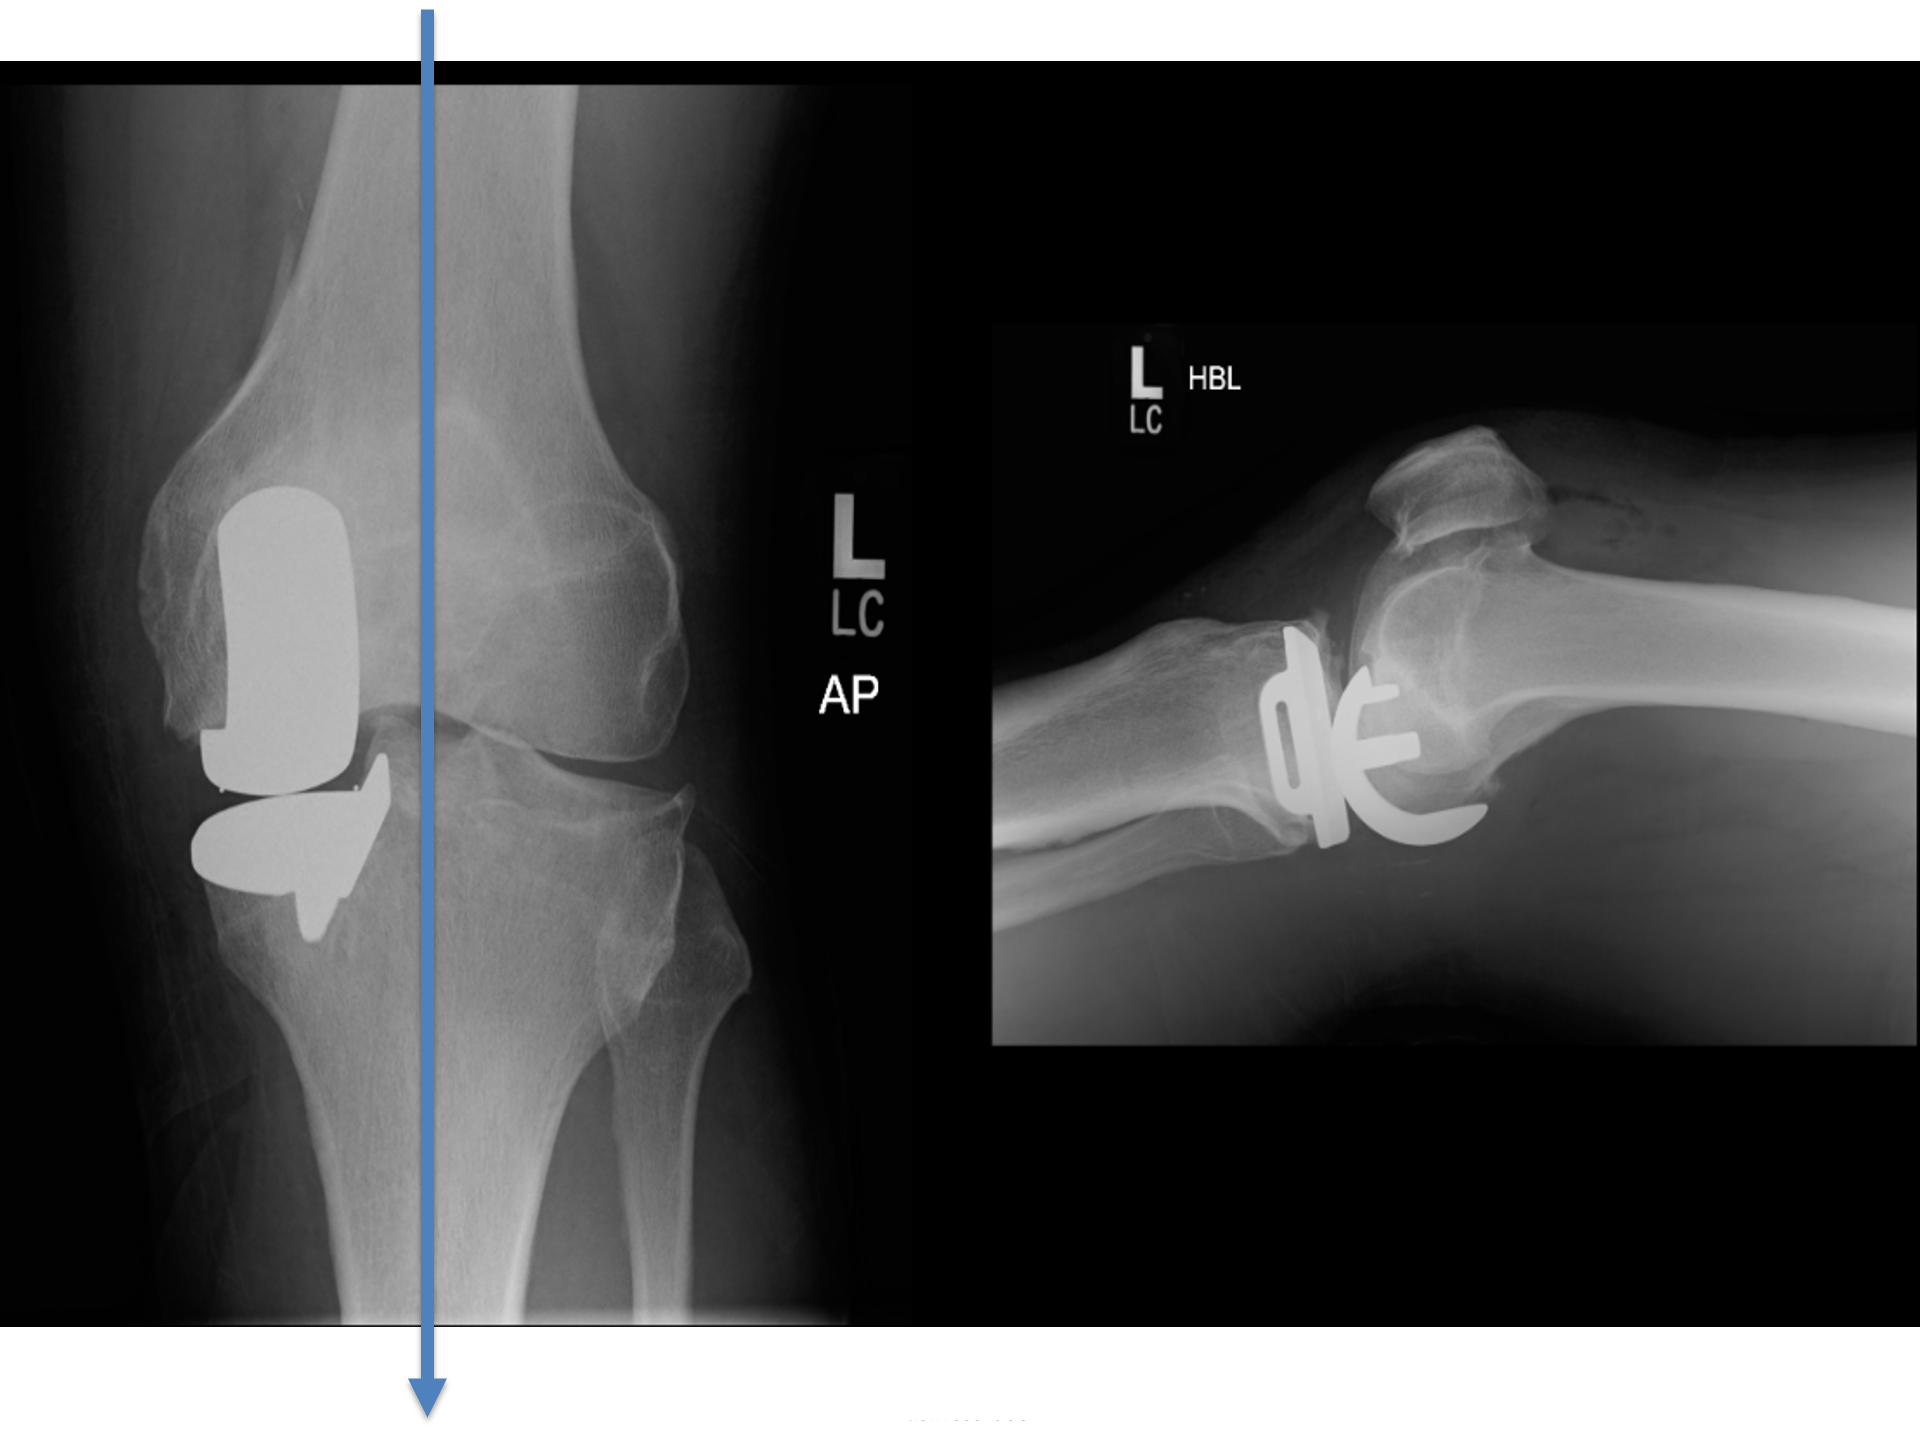

Intact ligaments restrict cartilage loss to a characteristic pattern that guides treatment.

Dai wanted did NOT want to risk progression (like

Marie's knee last week). So, here's his

partial knee replacement..